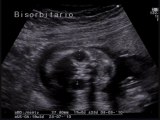

Aloka- Cuore sinistro ipoplasico

Cuore sinistro ipoplasico e persistenza della vena cava superiore sinistra

Cuore sinistro ipoplasico